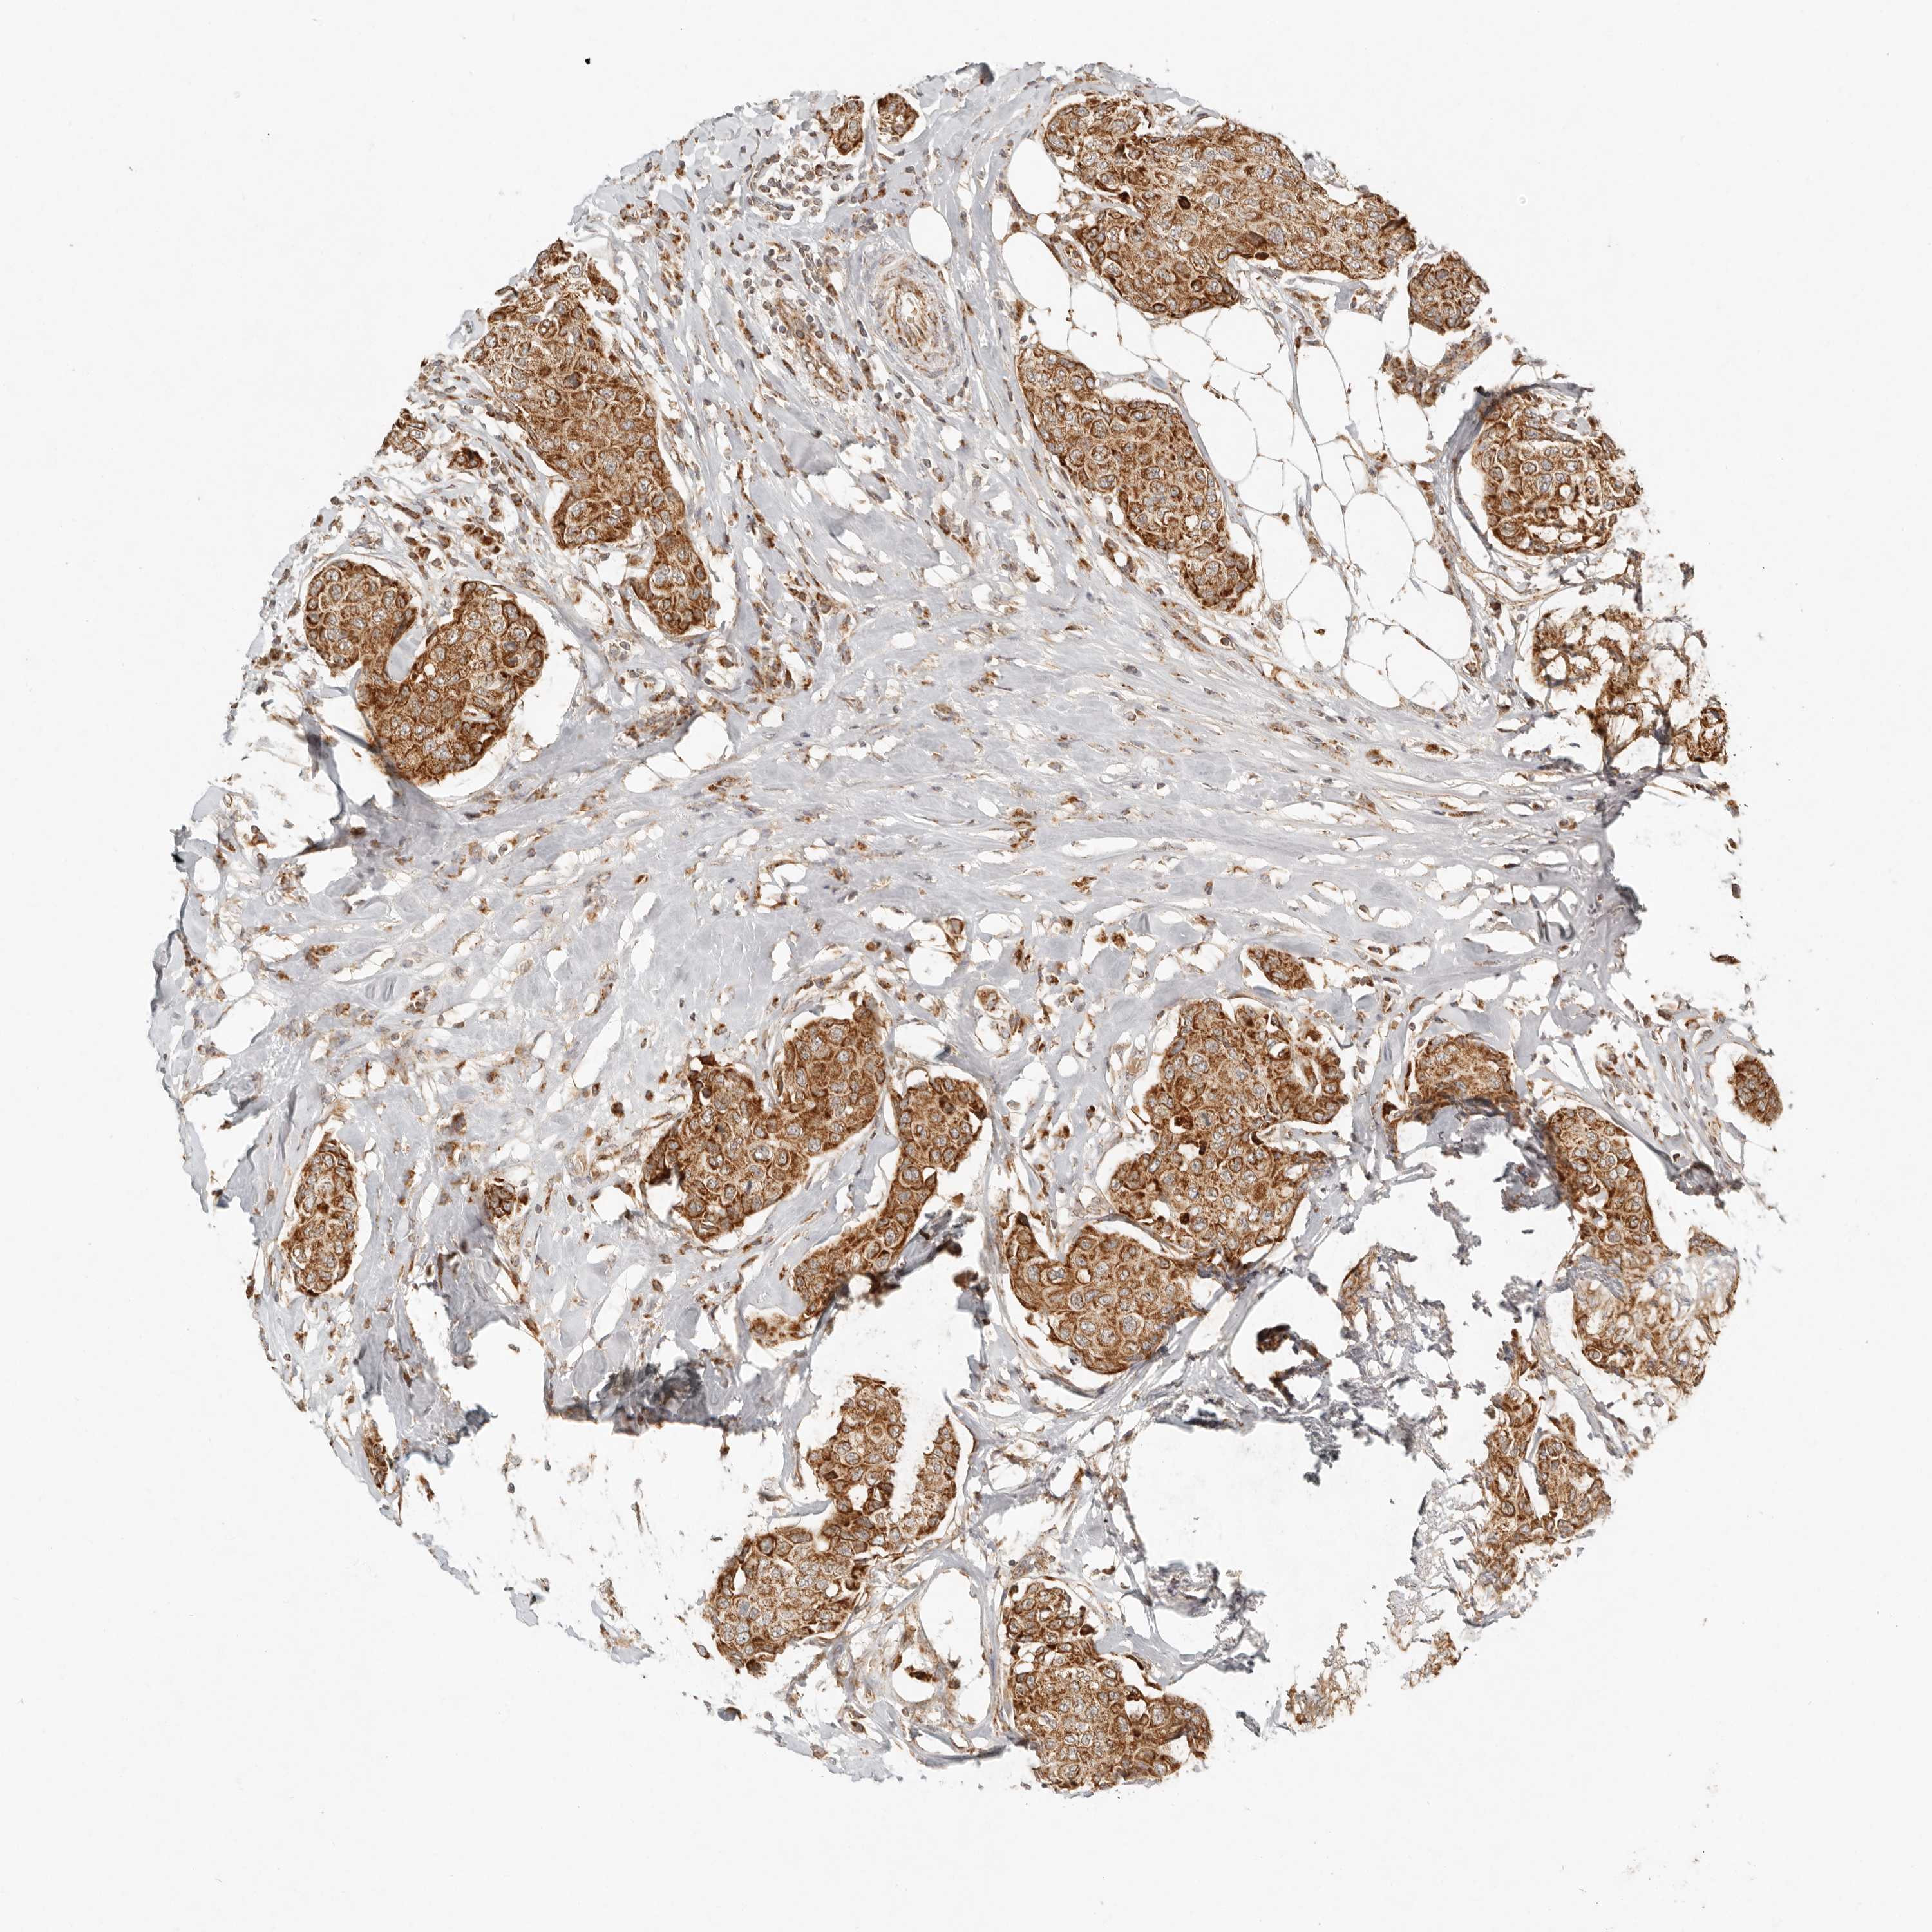

CANCER BREAST CANCER Show tissue menu

BRCA TCGA BRCA VALIDATION PROTEIN EXPRESSION